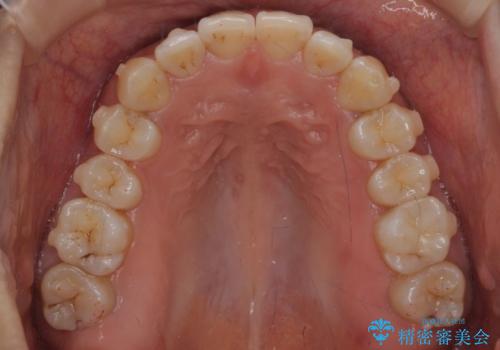

下の前歯のがたつき インビザラインで

- 前歯のがたつきを主訴に来院。

インビザラインで上下の前歯をわずかに削って並べました。

下の歯の叢生を並べると多少ブラックトライアングルがでることがあります。